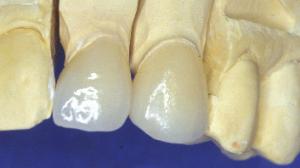

Céramique Empress. Réalisation prothétique: Naturel IDM, Paris.

Résultat final après collage.